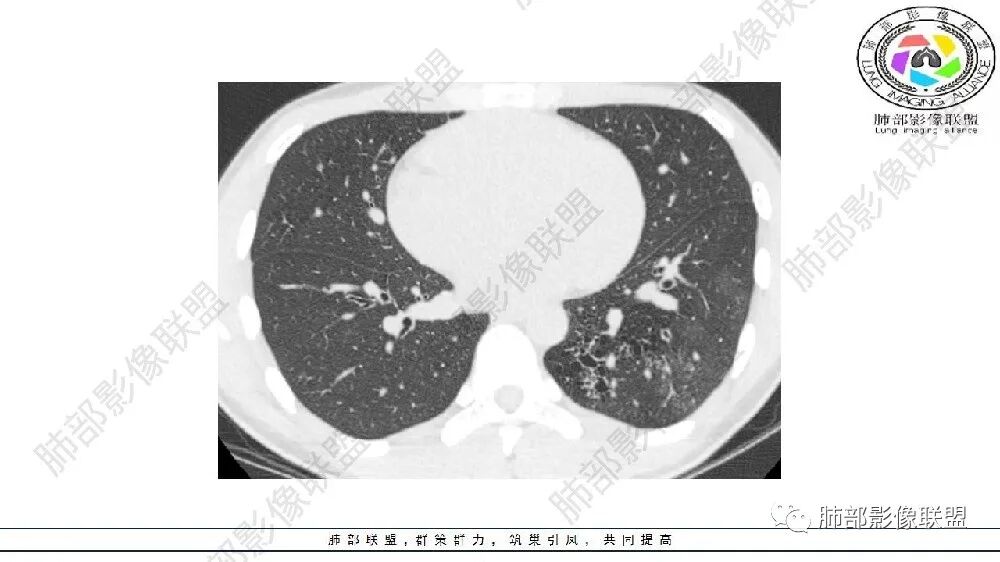

左肺下叶多发大小不等囊腔,周围伴有磨玻璃影,考虑CCAM伴感染。

左肺下叶多发大小不等囊腔伴周围磨玻璃影,可见血管增粗,似与胸主动脉相连,考虑肺隔离症,鉴别CPAM。

左肺下叶多发大小不等囊腔,囊壁略厚。周围见片状高密度影,边缘模糊不清,考虑CCAM伴感染,鉴别隔离症

左肺下叶多发囊腔、结节,及磨玻璃密度影,考虑肺隔离症,鉴别CCAM

左肺下叶多发大小不等囊腔,部分有粘液栓,周围伴有磨玻璃影,左肺下叶基底干支气管未见,双肺尖可见多发局限性透亮区,青年男性,考虑先天性气道或肺部发育畸形,支气管闭锁?CPAM?鉴别肺隔离症。

左肺下叶多发囊腔、斑片、索条(粗大扭曲的血管?)降主动脉左侧有血管影?首先考虑肺隔离症,建议增强扫描,鉴别囊腺瘤样畸形

左肺下叶多发薄壁囊性病灶,血管贴边,并多发增粗的血管,还有一些斑片影,磨玻璃影;两肺尖也有薄壁囊性病灶;病史咳嗽咳痰,痰中带血,跟老师们考虑肺隔离症伴感染,鉴别LIP

左肺下叶多发囊腔,粗大血管影,隔离征可能,鉴别气道畸形。

青年男性,左肺下叶多发囊腔伴磨玻璃影,并见增粗血管影,考虑肺隔离症。